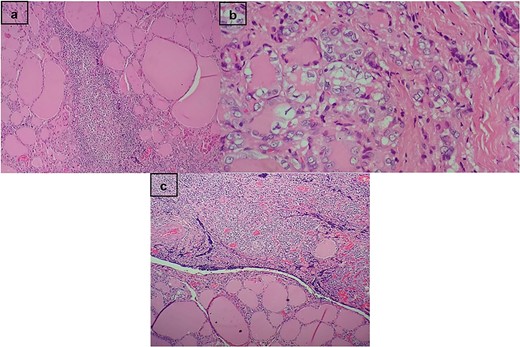

Histopathology results of the resected left lobe revealed a unifocal tall-cell variant micropapillary thyroid cancer measuring 0.4 cm without gross extrathyroidal extension (T1aN0M0). Additionally, evidence of Hashimoto’s thyroiditis and lymphocytic proliferation, suggestive of lymphoma, was observed but remained inconclusive for starting treatment (Fig. 3). Immunohistochemistry confirmed the diffuse large B-cell lymphoma diagnosis, with the specimen showing CD20 and BCL2 positivity and CD10 and CD30 negativity. Whole-body tomography was performed to determine the Ann Arbor lymphoma stage, which was classified as stage IE (localized involvement of a single extralymphatic organ in the absence of any lymph node involvement).

(a) Hashimoto’s thyroiditis. In the stroma, the presence of lymphoid follicles with germinal centers. (b) Follicular pattern papillary carcinoma. Empty nuclei, cleaved with bars and intranuclear inclusions. (c) Transition between the thyroid gland and dense proliferation of lymphocytes.